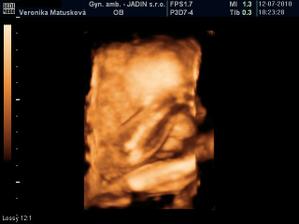

Adamko - 3D/4D

No tot vidno, že je náš syn, sa hanbil a hanbil až sa ukazovať nechcel....ale niekedy sa to podarilo, aj ked to nie je nejaká sláva. Pán doktor nám potvrdil chlapčeka, tak sme radi, vajká ukazoval ako len vedel len toho pipíka stále schovával. Ale je to za nami, pán doktor nás pekne popísal čo je kde, poodmeral nás a povedal, že je všetko v poriadku.